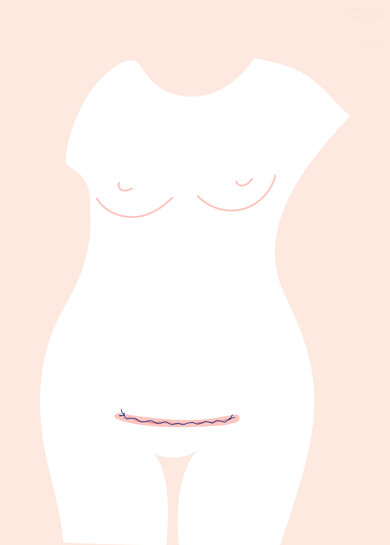

Wundheilung

Neben der Sorge um die Gesundheit des Babys sind Geburtsverletzungen wohl das, was vielen Frauen Angst macht. Gynäkologin Anna Stamm beruhigt: „In den allermeisten Fällen sind die Verletzungen sechs bis acht Wochen nach der Geburt verheilt.“ Auch der sichtbare Teil einer Kaiserschnittnarbe ist dann abgeheilt. Zunächst ist die Narbe noch rot, verblasst aber innerhalb von sechs bis zwölf Monaten. „Um die Narbe herum fühlt sich die Haut oft taub an“, sagt Stamm. „Das kann bis zu ein Jahr lang dauern. Das Gefühl kommt aber nicht immer zurück.“ Bis sich der Körper annähernd anfühlt wie vor dem Kaiserschnitt, kann viel Zeit vergehen. Das gilt auch für schwere Dammverletzungen. Schwellungen der Vagina und Vulva bessern sich meist nach wenigen Tagen deutlich.